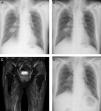

The patient is an 83-year-old non-smoking man who was diagnosed with prostate cancer at age 80 years and treated with brachytherapy for 2 years. At age 83 years, he presented with an abnormal chest X-ray (CXR) during routine follow up (Fig. 1A). Chest computed tomography (CT) revealed a 30.5mm×30.5mm mass in the right lower portion of the lung that crossed over into the adjacent middle lobe and thickened interlobular septa in the right middle and lower lobes. 18F-fluorodeoxyglucose (FDG) positron emission tomography/CT showed intense FDG uptake on both sides of the hilar and mediastinal lymph nodes. Magnetic resonance imaging (MRI) with contrast did not reveal any brain metastases. Fiberoptic bronchoscopy revealed lung adenocarcinoma. The patient was clinically staged as T2aN3M1a, stage IVA. Although no sensitizing EGFR mutations or ALK translocations were detected, the PD-L1 tumor proportion score was 95%, and the patient's Eastern Cooperative Oncology Group performance-status score was 0. Thus, we selected pembrolizumab at a dose of 200mg every 3 weeks as the first-line treatment. CXR showed a decrease in pulmonary mass size 5 days after initial pembrolizumab administration (Fig. 1B); however, the patient presented with myalgia of both proximal femurs and lower back pain 1 week after the second cycle of pembrolizumab. Two days before admission, he developed right ptosis. At admission, he was unable to walk without assistance, because of myalgia. Physical examination revealed symmetric weakness of the deltoid (medical research council [MRC] 4) and iliopsoas (MRC 4+) with hoarseness and mild dysphagia. He was administered bethanechol 25mg twice daily, silodosin 4mg twice daily, benidipine 4mg once daily, rosuvastatin 2.5mg once daily, and alfacalcidol 1μg once daily. Initial laboratory test results revealed elevated levels of creatine kinase (CK) 6417IU/L (62–287IU/L), CK-MB 176IU/L (0–25IU/L), and aldolase 74.7IU/L (2.1–6.1IU/L). The levels of thyroid-stimulating hormone and free thyroxine were within normal ranges. Test results for anti-aminoacyl tRNA synthase antibody, anti-acetylcholine receptor (AChR) antibody, and anti-muscle-specific kinase (MuSK) antibody were negative. At admission, rosuvastatin was discontinued. Short-tau inversion recovery MRI of the femur revealed diffuse increased signal in the gluteal and thigh muscles (Fig. 1C). Repetitive nerve stimulation test did not reveal gradual amplitude reduction (waning) and increment (waxing) of compound muscle action potentials. Edrophonium test results were negative. Muscle biopsy from the left musculus quadriceps femoris revealed lymphohistiocytic infiltration with muscle atrophy. The patient was then diagnosed with rhabdomyolysis with myositis, a suspected immune-related toxicity. We discontinued pembrolizumab and initiated systemic prednisone (40mg/day) soon after the muscle biopsy. Serum CK level was normalized within 3 weeks after prednisone administration. Myalgia and ptosis improved within 4 weeks after prednisone administration. CXR showed continuous decrease in pulmonary mass size 2 months after initial pembrolizumab administration (Fig. 1D). However, his performance-status score decreased from 0 to 2.